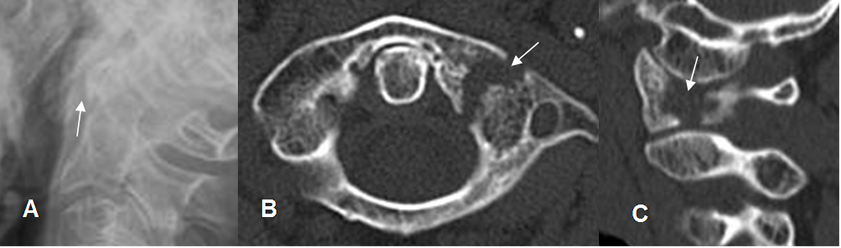

Fig 194. Fractura de C1.

A: Rx lateral. Alteración en la configuración de la articulación atlanto-axoidea.

B: TAC axial y C: TAC reconstrucción sagital. Fractura en el lado izquierdo, del arco anterior de C1.